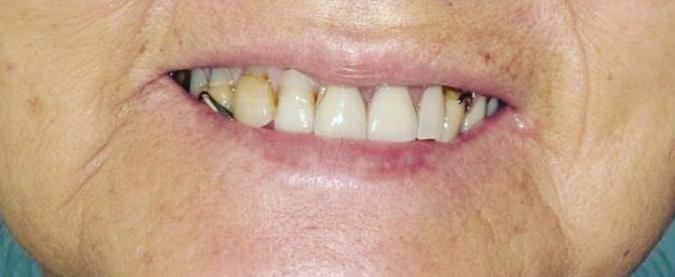

Submitted By Sivakumar Sreenivasan, DMD, MDS

Dental Implant Center of Rockville

Can just four implants replace all of the teeth on the top or the bottom of your mouth? Thanks to advances in dental implant technology, that answer is a resounding yes.

Believe it or not, tooth loss is extremely common among adults, especially as we age. In fact, more than 35 million people in America are missing all of their upper and/or lower teeth. Rather than living with the discomfort and hassles of dentures, many people are opting for what is called “all-onfour” dental implant restoration.

All-On-Four: One Full Arch Of Teeth, Four Dental Implants

Here’s where it gets really interesting: You do not need a dental implant for each and every one of your missing teeth. All you need is four precisely placed implants on the top of your mouth, and four on the bottom, to restore your full smile. That’s the beauty of the all-on-four. And because the implant is made of titanium, it has the unique ability to fuse to living bone and function as part of it. So eventually, the dental implant becomes part of the jawbone and serves as a strong, long-lasting foundation for your new teeth.

this bone fusion has another important benefit: it prevents future bone loss in the jaw. This helps to maintain a more youthful facial structure – and better oral health. But perhaps the biggest surprise about the all-on-four is how quickly it can transform your life.